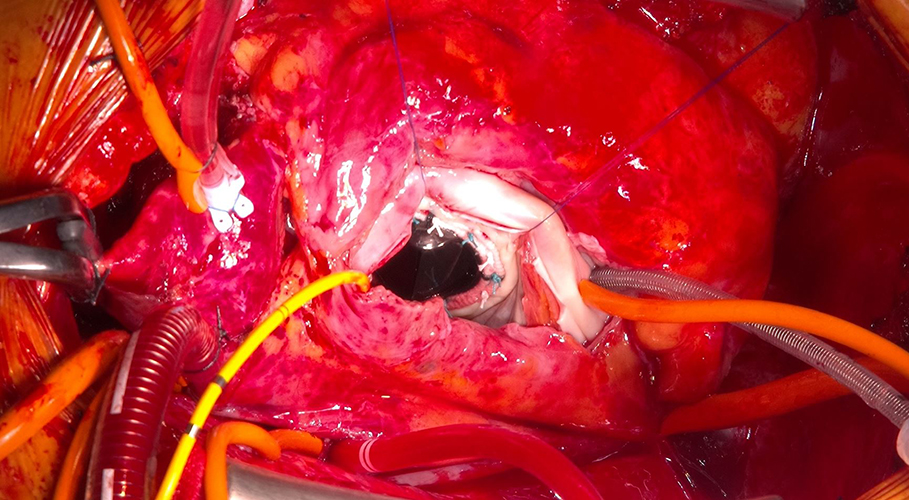

- 先天性心疾患術後の成人期再手術(※画像1、2、3)

画像3画像1、2、3 幼少期ファロー四徴症手術後の方。僧帽弁閉鎖不全症、三尖弁閉鎖不全症、肺動脈弁閉鎖不全症に対する僧帽弁置換術、三尖弁形成術、肺動脈弁置換術